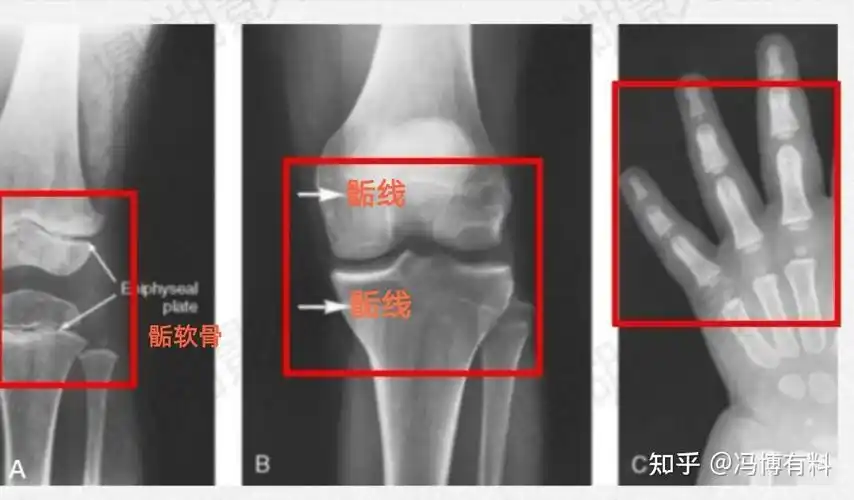

儿童长骨解剖 骨骺板是指儿童时期骨骺与干骺端之间的软骨组织 有生长

一种我们叫软骨生长,长骨的末端有一个软骨板,也叫骨骺板

它会随着年龄的增长而逐渐变短,当骨骺与干骺端的软骨完全骨化后就

青春期结束以后骺软骨全部骨化,骨干和骨骺连成一体,骨骼完全钙化,骨

当生长板软骨细胞停止增殖,骺软骨完全被骨组织取代,在长骨的骨干和